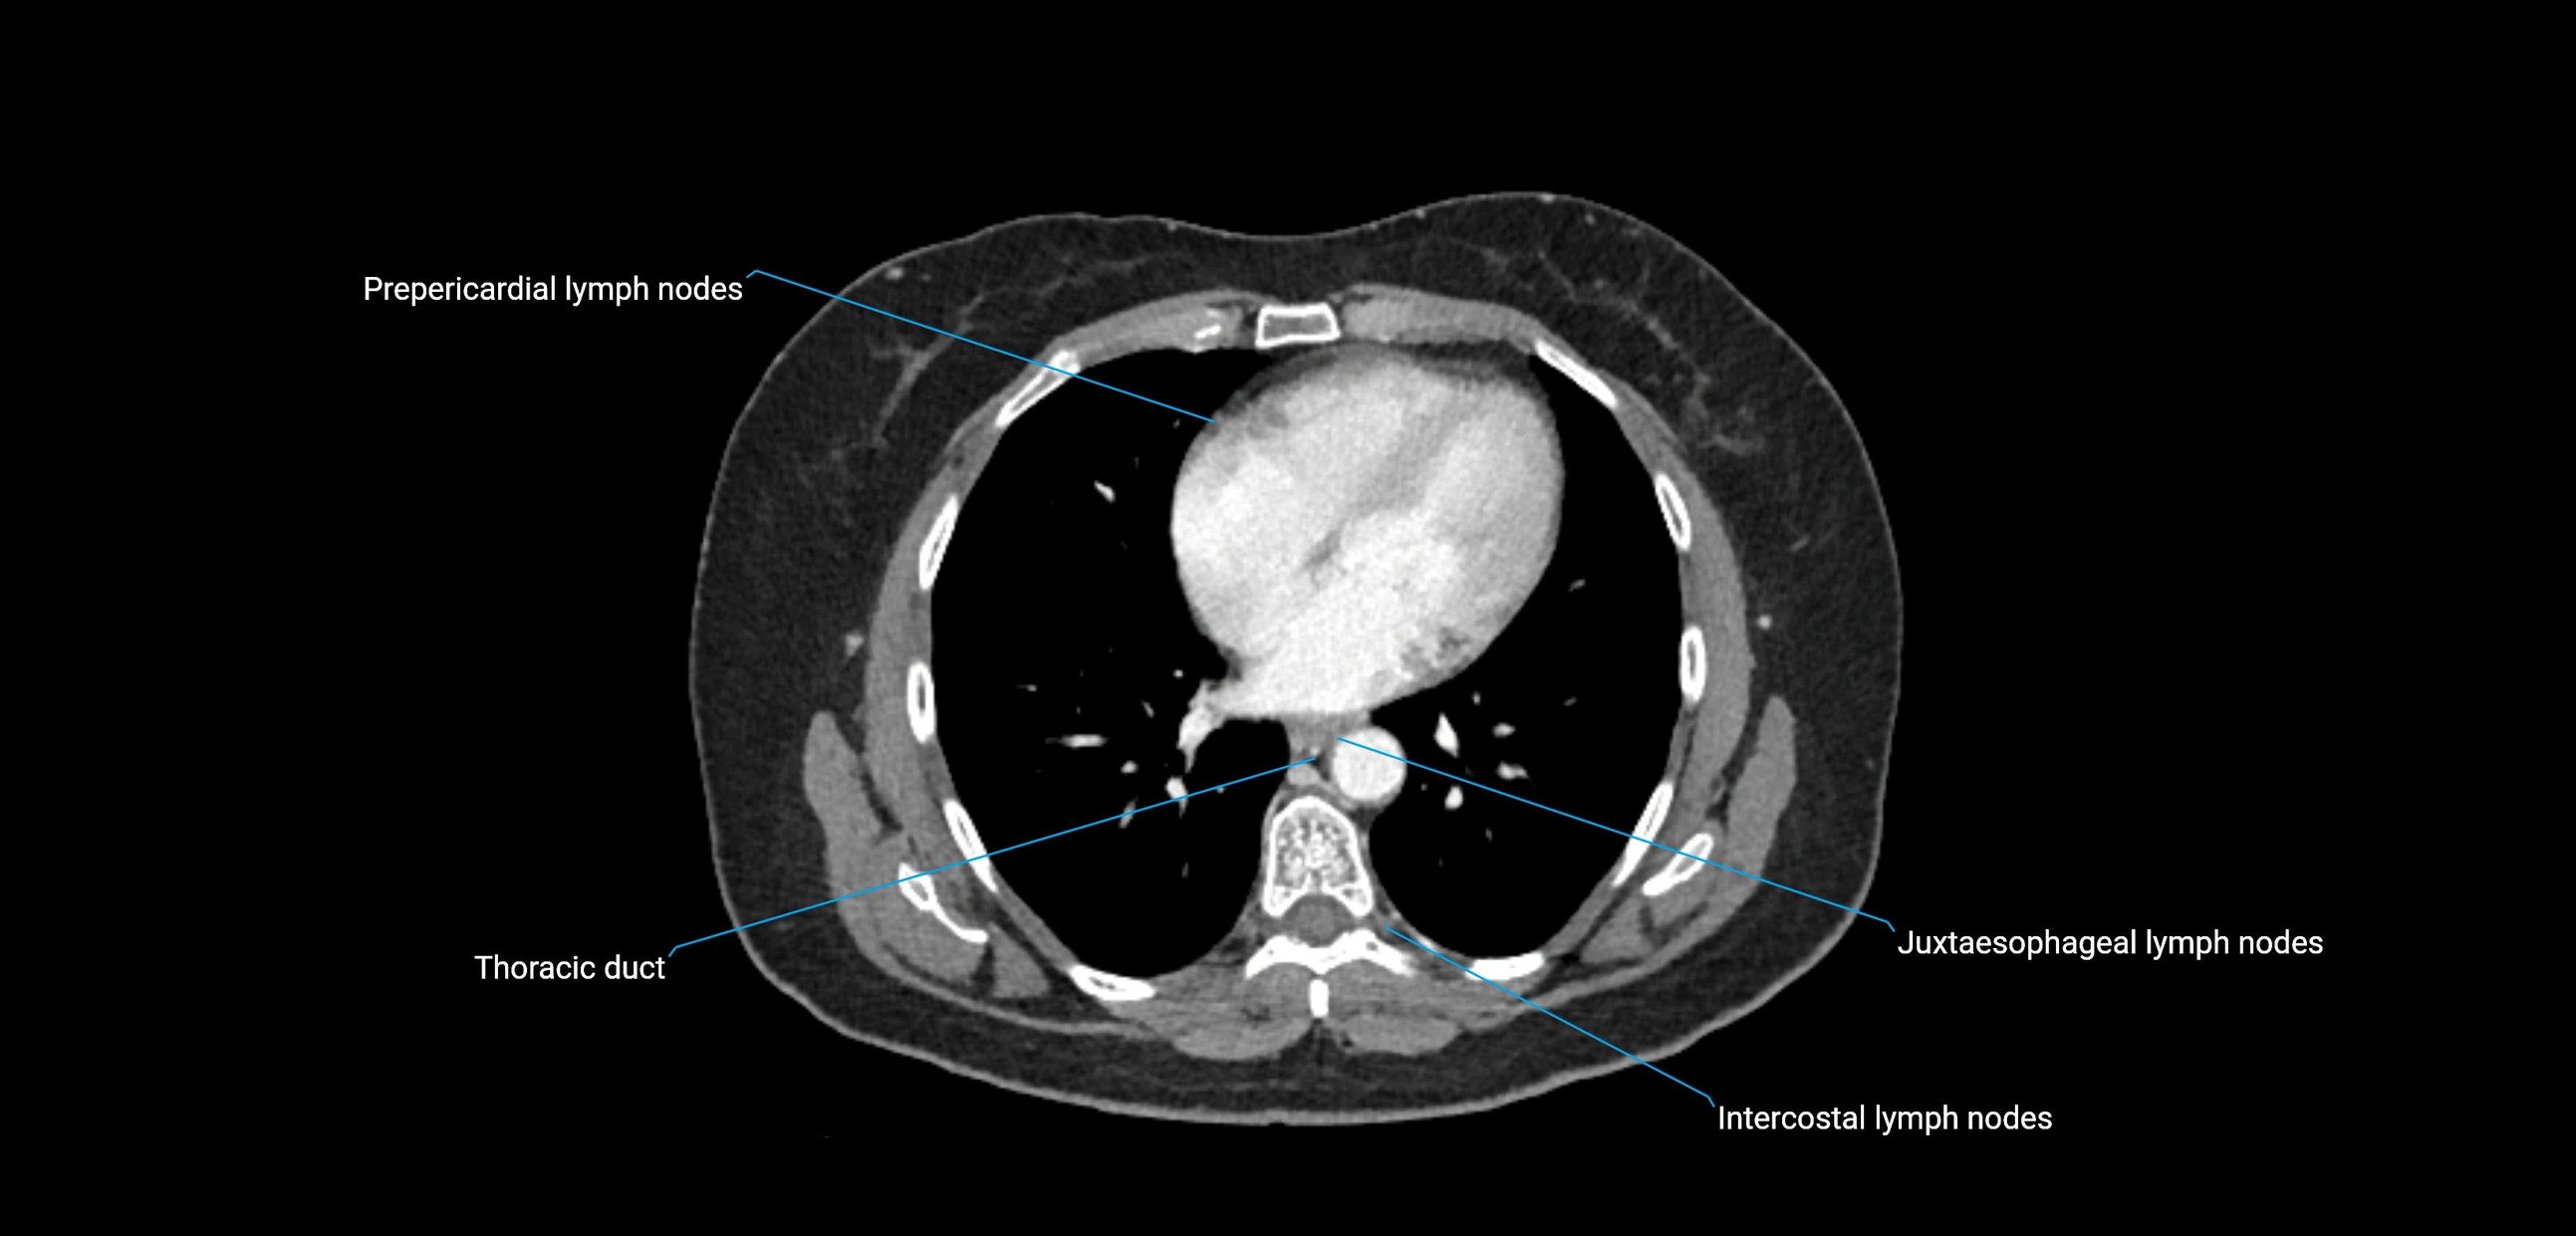

CT image

image